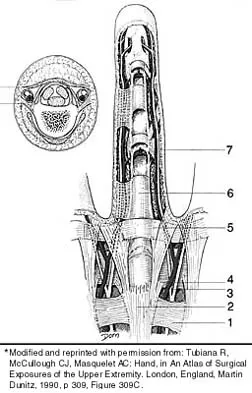

Which of the following anatomic structures is labeled 6 in Figure 27?

Explanation